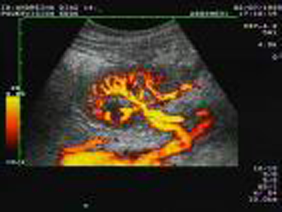

Ultrasonido 4D HD live y Doppler color. El equipo de ultrasonido cuenta con tecnología de punta con la capacidad de utilizar 3ra y 4ta dimensión apreciando al bebe en tiempo real y en movimiento con una claridad increíble, logrando visualizar cada detalle incluso del rostro. Así mismo cuenta con modalidad Doppler color, angio-doppler y doppler pulsado lo cual nos permite verificar cualquier vaso sanguíneo del organismo, su velocidad dirección y resistencia de flujos

Cuenta con múltiples transductores para revisar órganos superficiales y órganos profundos. Con este equipo se pueden realizar todos los estudios necesarios para auxiliar al médico en la optima resolución de sus diagnósticos.